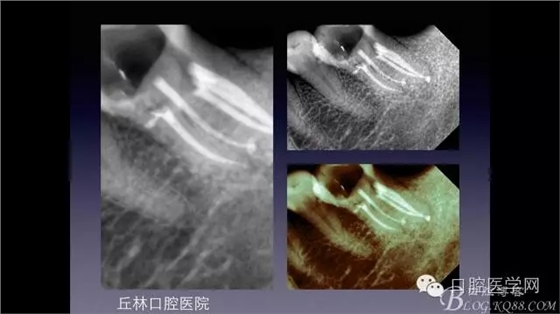

一例36根管再治療,五個(gè)根管冷側(cè)加壓病例